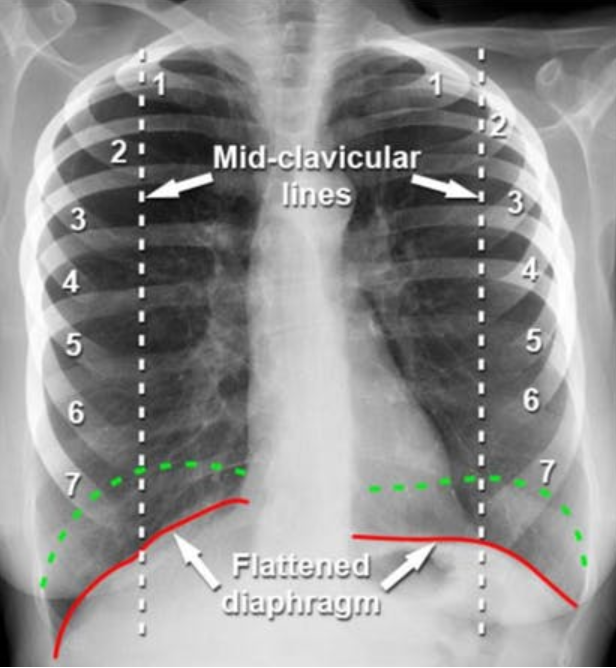

What are the differences between these 2 x-ray images?

Differences:

Flattened diaphragm

Heart looks smaller - more elongated and narrowed

Hyperexpanded chest - hyperinflation signs that can be seen on an x-ray, more than 7 anterior ribs visible at the midclavicular line, flattened diaphragm, heart may appear smaller and narrowed as the lung tissue has moved down as it so full and pulls down th eheart with it.